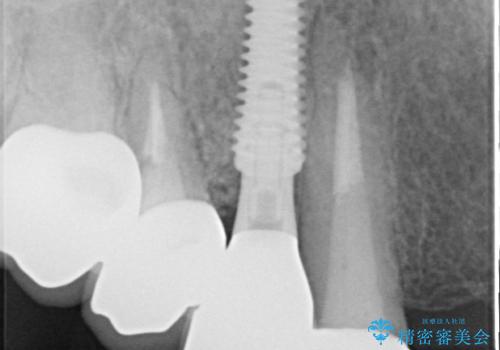

診察したところ、歯根に破折線が確認され抜歯が必要な状態でした。

歯肉や歯槽骨の状態は良好であったため、抜歯即時埋入インプラントによる補綴治療を行うこととしました。

膿の出口が認められた頬側の歯槽骨は欠損が大きかったものの、インプラント埋入には十分な骨があり、無事に短期間で治療を終えることができました。